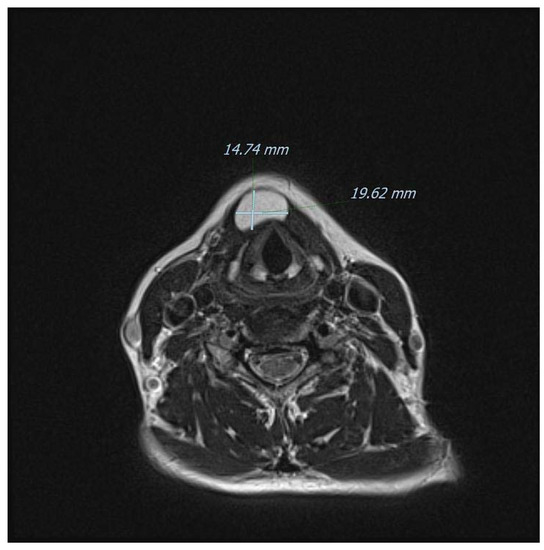

Figure 6.

Another T2-weighted axial view of the mass on MRI. Ultrasonography is considered to yield a high diagnostic accuracy for subcutaneous lipomas (sensitivity of 88.1%; specificity of 99.3%) [13], but in our case, it was inaccurate in defining the boundaries of the lesion and therefore the surgical planning. Modern CT and MRI techniques offer instead a superb definition of the anatomical relationships as well as a very strong correlation with final histopathology, especially in children [14]. Furthermore, and for midline neck masses only, the role of fine-needle aspiration cytology/biopsy (FNAC/FNAB) remains debatable even for the common TGD cysts: for instance, a retrospective evaluation at the Johns Hopkins Department of Pathology found a diagnostic sensitivity of only 62%, with a calculated positive predictive value of 69% [15,16]. Additionally, imaging remains fundamental to exclude a rarely coexisting carcinoma (usually papillary-type), that usually occurs in patients 40 years of age or older. In detail, classically described features of a suspected malignancy include enhancing solid nodular masses (more frequently observed) and/or calcifications (more specific) within the TGD cyst [6]. Sistrunk’s operation remains the mainstay of management for TGD cysts because it has been shown to reduce the risk of recurrence down to 3–10% of adult cases, [17,18,19] and to around 20% in children [20]. There is also a non-negligible rate of postoperative complications and, in a recent large pediatric American series, postoperative rates of cervical seroma, local infection, and need for surgical revision were reported to be 9.5%, 7%, and 7.6%, respectively [21]. For other conditions associated with the TGD remnants instead, the evidence regarding the best surgical approach is weaker. For example, midline dermoid cysts usually require simple excision without sacrificing the hyoid bone and a preoperative differential diagnosis is now feasible by exploiting the diffusion-weighted imaging (DWI) technique with MRI, or even with ultrasound alone [22,23]. Interestingly, the two lesions may in very rare cases occur at the same time; therefore, some surgeons prefer to perform Sistrunk’s operation for every central (pediatric) neck mass [24,25]. The absence of thyroid tissue in our case might be viewed as a complete lipomatous degeneration of a TGD remnant, as speculated by Tsai and colleagues [10]. However, we currently have no preoperative imaging methods to determine whether thyroid cells are present in these kinds of neck masses unless they are metabolically active and therefore visible on scintigraphy [26]. In the present case, scintigraphy was not performed nor it was available in the study by Tsai et al. [10]. Indeed, the use of a “blind scintigraphy” may constitute an interesting approach in the work-up of midline masses, but the available experience in this regard is limited. It must also be remembered that even in classical TGD cysts, thyroid tissue in the form of follicles or scattered cells are found only in around 50% of cases [27].